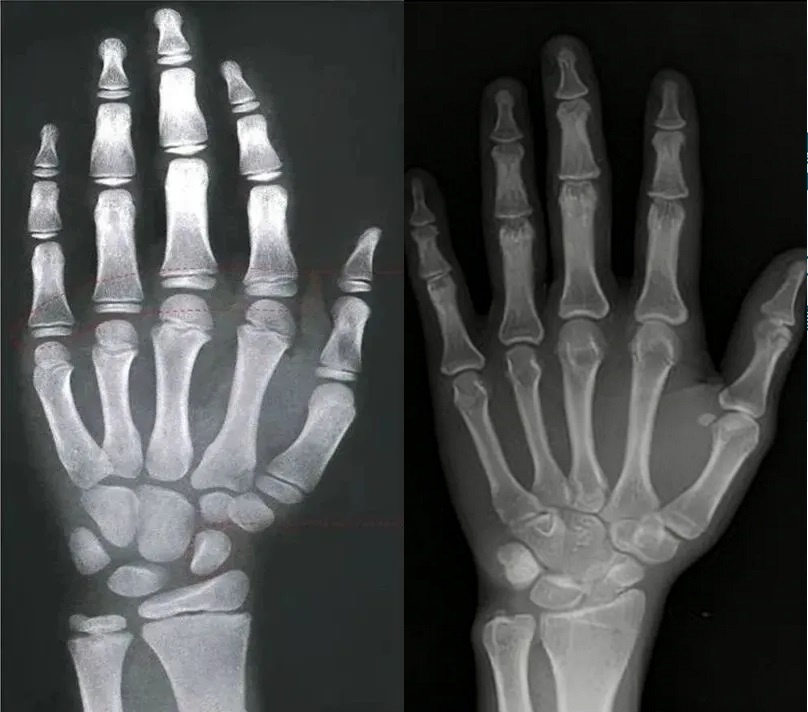

Bản chất của tăng trưởng chiều cao là sự phân chia và cốt hóa liên tục của các tế bào sụn ở đầu xương dài (như xương đùi và xương chày). Sụn này xuất hiện dưới dạng một "đường" mờ trên phim X-quang, đó chính là đường sụn đầu xương. Khi đường sụn đầu xương cốt hóa hoàn toàn và đóng lại, sự tăng trưởng chiều cao về cơ bản sẽ dừng lại.

Hình ảnh chụp X-quang cổ tay trái: các sụn đầu xương chưa đóng, trẻ vẫn còn tiềm năng phát triển (ảnh trái) và các sụn đầu xương đã đóng, chiều cao về cơ bản đã cố định (ảnh phải). Ảnh: QQ News.

Cách chính xác nhất để xác định điều này là chụp X-quang cổ tay trái để quan sát tình trạng đóng sụn đầu xương.

Nếu phim X-quang cho thấy các sụn đầu xương chưa đóng lại, điều đó cho thấy trẻ vẫn còn tiềm năng phát triển; nếu chúng đã đóng hoàn toàn, chiều cao về cơ bản đã được cố định. Ngay cả khi trẻ thực sự còn nhỏ tuổi, nếu tuổi xương của trẻ đã phát triển và gần đóng sụn đầu xương, tiềm năng phát triển của trẻ sẽ bị hạn chế.